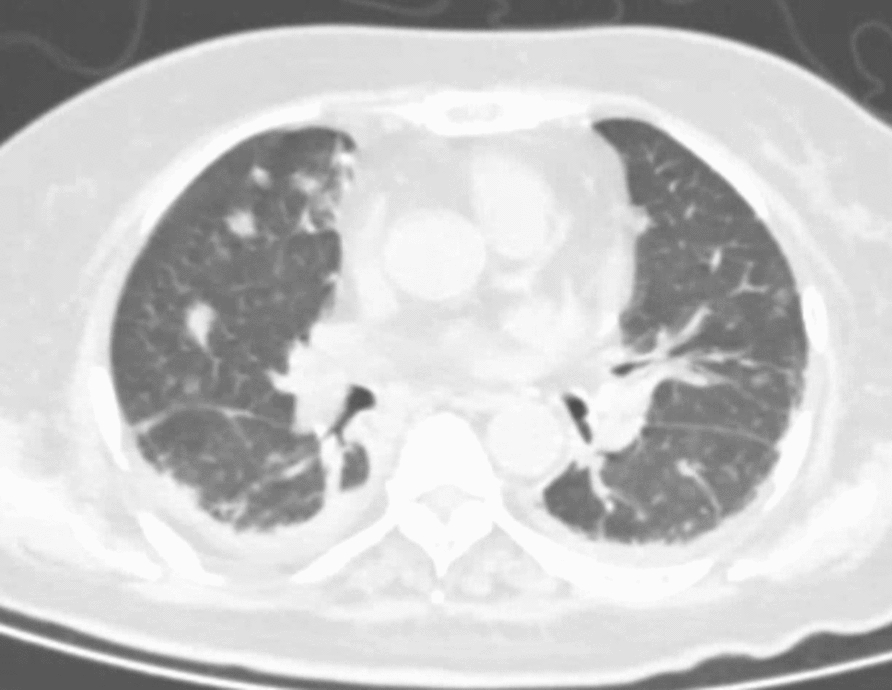

Case report: A 75-year-old Han Chinese female patient who presented to the emergency department primarily for fever accompanied by chills was diagnosed with pyogenic liver abscess complicated with pulmonary infection, involving multiple pus emboli in the branches of the right hepatic vein. The patient accepted intravenous imipenem and cilastatin sodium for anti-infection, and subcutaneous insulin to control hyperglycemia. Percutaneous liver puncture and drainage was performed under ultrasound guidance. During the treatment the patient presented with headache, weakness in both lower limbs and lower back pain. Brain magnetic resonance imaging showed intracranial infection and lumbar magnetic resonance imaging showed infection of the vertebral body, intervertebral disc, and soft tissue. The patient had a liver abscess positive for Klebsiella pneumoniae together with infection of other organs, thus she was eventually diagnosed with invasive Klebsiella pneumoniae liver abscess syndrome. The antibiotics were adjusted according to the site of infection and drug sensitivity test. The patient recovered after percutaneous liver puncture and drainage under ultrasound guidance and anti-infection treatment for 3 months. Reexamination of abdominal computed tomography, chest computed tomography, brain magnetic resonance imaging and lumbar magnetic resonance imaging suggested that the infectious lesions had disappeared.